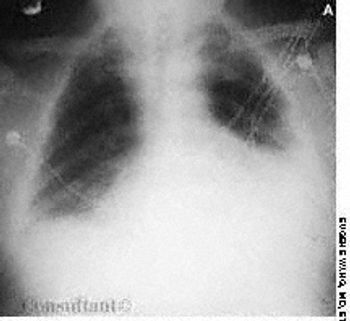

A 60-year-old white man was evaluated for dyspnea on exertion. Hepatomegaly and abnormal skin pigmentation were noted, particularly in the upper extremities.